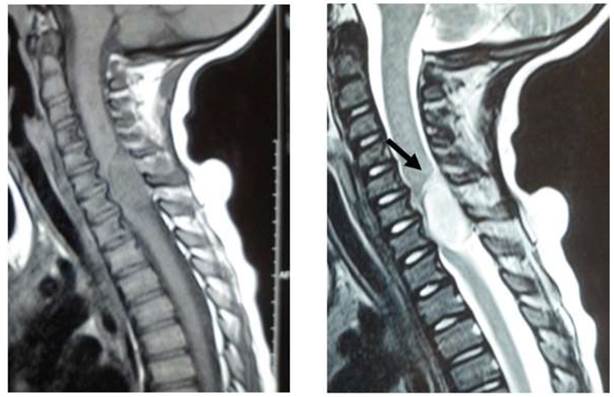

Se solicita Resonancia Nuclear Magnética (RNM) de columna cervical, dorsal y lumbar que evidencia lesión sólida, intrarraquídea, localizada en raquis cérvico-dorsal, desde C6 a T1, que compromete el espacio intradural a derecha, extendiéndose al foramen C6-C7, el cual está aumentado de calibre. En este nivel el proceso adopta el aspecto en reloj de arena, comprimiendo el eje medular, el cual se encuentra lateralizado a izquierda, de señal conservada. La lesión es bien limitada con una extensión total de 22cm. Se presenta isointensa con el tejido muscular en las secuencias T1 e hiperintensa en las secuencias T2. Luego de la administración del contraste intravenoso se observa intenso realce del mismo. Los segmentos vertebrales y los discos intervertebrales cervicales, dorsales y lumbares son de aspecto y señal conservadas. El cono medular se localiza a la altura de L1. En suma: lesión sólida intradural, extramedular, centrada en C6-C7, con extensión al foramen derecho.

En nuestro medio, no se dispone de comunicaciones de casos con neurofibromas plexiformes intradurales. Figura 1.

Figuras. 1: RNM de columna cervicodorsal con y sin contraste donde se observa lesión intraraquídea que comprime eje medular C6- T1.